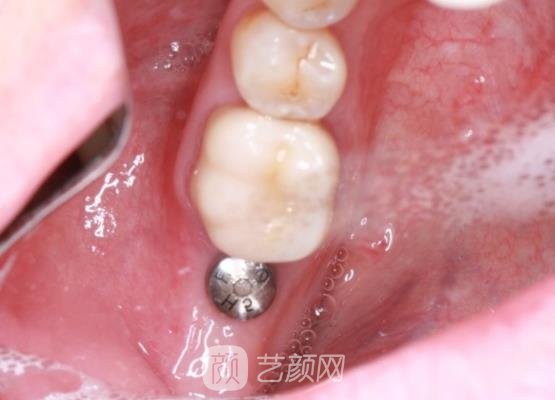

因为我的牙齿掉了半颗,所以需要把这半颗牙齿拔掉之后再进行牙齿的种植,是比较麻烦的,而且我还要挑选种植牙的材质,这样手术的成果才可以比较理想,挑选完之后,医生就帮我开始了手术。

刚结束手术的时候,我的牙龈处还有一些疼痛的感觉,牙齿很无力,咬合的时候真的很不舒服,而且口腔里边也有一些异物的感觉,医生告诉我这些情况比较正常,过几天以后我就会适应了,不用太过于担心。

几个月之后,我的种植牙已经恢复的很自然了,而且口腔里边也没有不舒服的感觉,手术的成果真的是让我太满意了,现在这颗种植牙就跟我自己天生的牙齿一样,一点儿都看不出来差别,成果真的是太棒了。